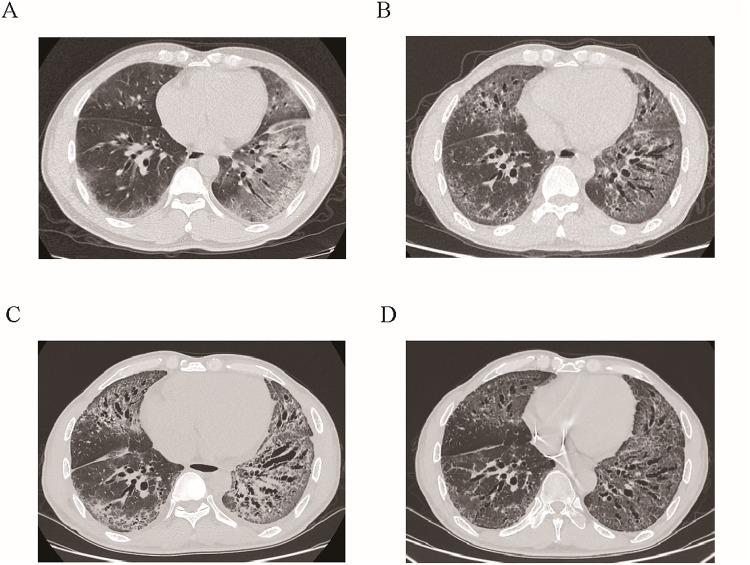

Results: The patient exhibited significant clinical improvements, including a reduction in cardiac size, restoration of sinus rhythm, and resolution of heart failure symptoms. ILD and skin sclerosis showed substantial regression. Pulmonary function tests indicated significant recovery in lung capacity and diffusion capacity. Additionally, gastrointestinal symptoms such as abdominal pain and bloating were completely resolved.